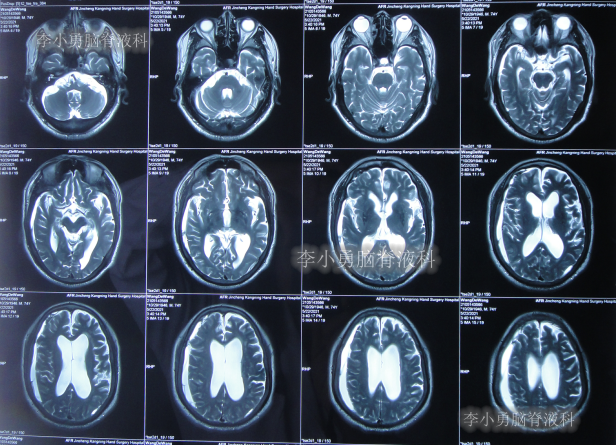

2020年10月29日(发病已8年),因症状一直没有得到改善且呈进行性加重趋势,查头部核磁示脑积水(图-1)。

图-1:2020年10月29日头部核磁